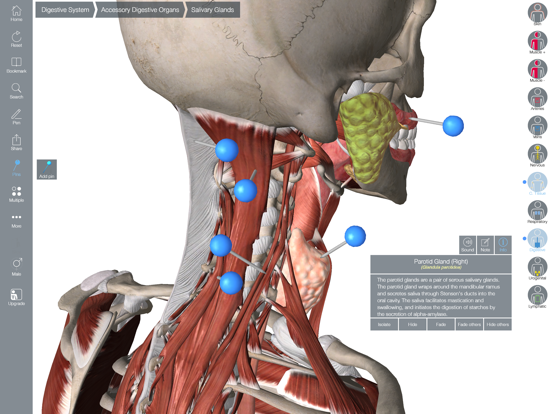

Downloading Essential Anatomy 5 IPA for iOS is a convenient and useful way to explore the world of human anatomy right from the comfort of your iPhone or iPad. This app provides a comprehensive and detailed view of the human body, allowing users to interact with various systems and structures. With stunning 3D graphics, it offers a visually captivating experience that aids in understanding and learning about the complexities of the human body. Whether you are a medical student, healthcare professional, or someone with a general interest in anatomy, Essential Anatomy 5 IPA is a must-have app that provides a wealth of knowledge at your fingertips. The app’s intuitive interface and easy navigation make it accessible to users of all levels of expertise. With just a few taps, you can delve into different layers of the body, explore various organs, muscles, and bones, and gain a deeper understanding of human anatomy. Download Essential Anatomy 5 IPA today and elevate your knowledge and appreciation of the human body.

The Essential Anatomy 5 IPA for iPhone is an incredible tool for medical students, professionals, and anyone interested in learning more about the human body. This app provides a comprehensive and detailed 3D model of the human anatomy, allowing users to explore and study different parts of the body with ease. With its user-friendly interface and interactive features, users can zoom in, rotate, and examine every angle of the human body, from bones and muscles to organs and systems. The app also provides in-depth information about each structure, making it a valuable resource for studying and understanding the intricacies of human anatomy. Whether you’re a medical student preparing for exams or simply curious about the wonders of the human body, the Essential Anatomy 5 IPA for iPhone is an essential tool to have at your fingertips.

Essential Anatomy 5 IPA MOD IOS is a revolutionary app that has changed the way we learn about the human body. With its advanced features and stunning visuals, this app provides an immersive and interactive experience for users. Whether you are a medical student, healthcare professional, or simply interested in learning about anatomy, Essential Anatomy 5 is a must-have tool. It offers a comprehensive library of detailed 3D models, allowing users to explore every aspect of the human body. From the skeletal system to the muscular system, nervous system to cardiovascular system, this app covers it all. Additionally, it provides in-depth information on each structure, including names, functions, and clinical relevance. With its user-friendly interface and intuitive controls, navigating through the app is a breeze. Overall, Essential Anatomy 5 IPA MOD IOS is an essential resource that brings anatomy to life, making it an invaluable tool for anyone interested in the human body.

This app provides a comprehensive and detailed 3D representation of the human body. With over 8,200 anatomical structures, including muscles, bones, organs, and more, it offers a level of accuracy and depth that is unparalleled. Whether you are studying for an exam or explaining a medical condition to a patient, Essential Anatomy 5 IPA has the information you need.

Essential Anatomy 5 IPA allows users to interact with the 3D models, zooming in and rotating them to explore every angle. The user-friendly interface makes navigating through the app a breeze, and the intuitive controls ensure that anyone, regardless of their level of expertise, can easily explore and understand the complex anatomical structures.

One of the standout features of Essential Anatomy 5 IPA is its ability to showcase cross-sectional views of the body. This enables users to see the internal structures and their relationships with each other, providing a deeper understanding of the body’s intricate systems. This feature is particularly useful for students learning about the different body cavities or professionals wanting to explain surgical procedures to their patients.